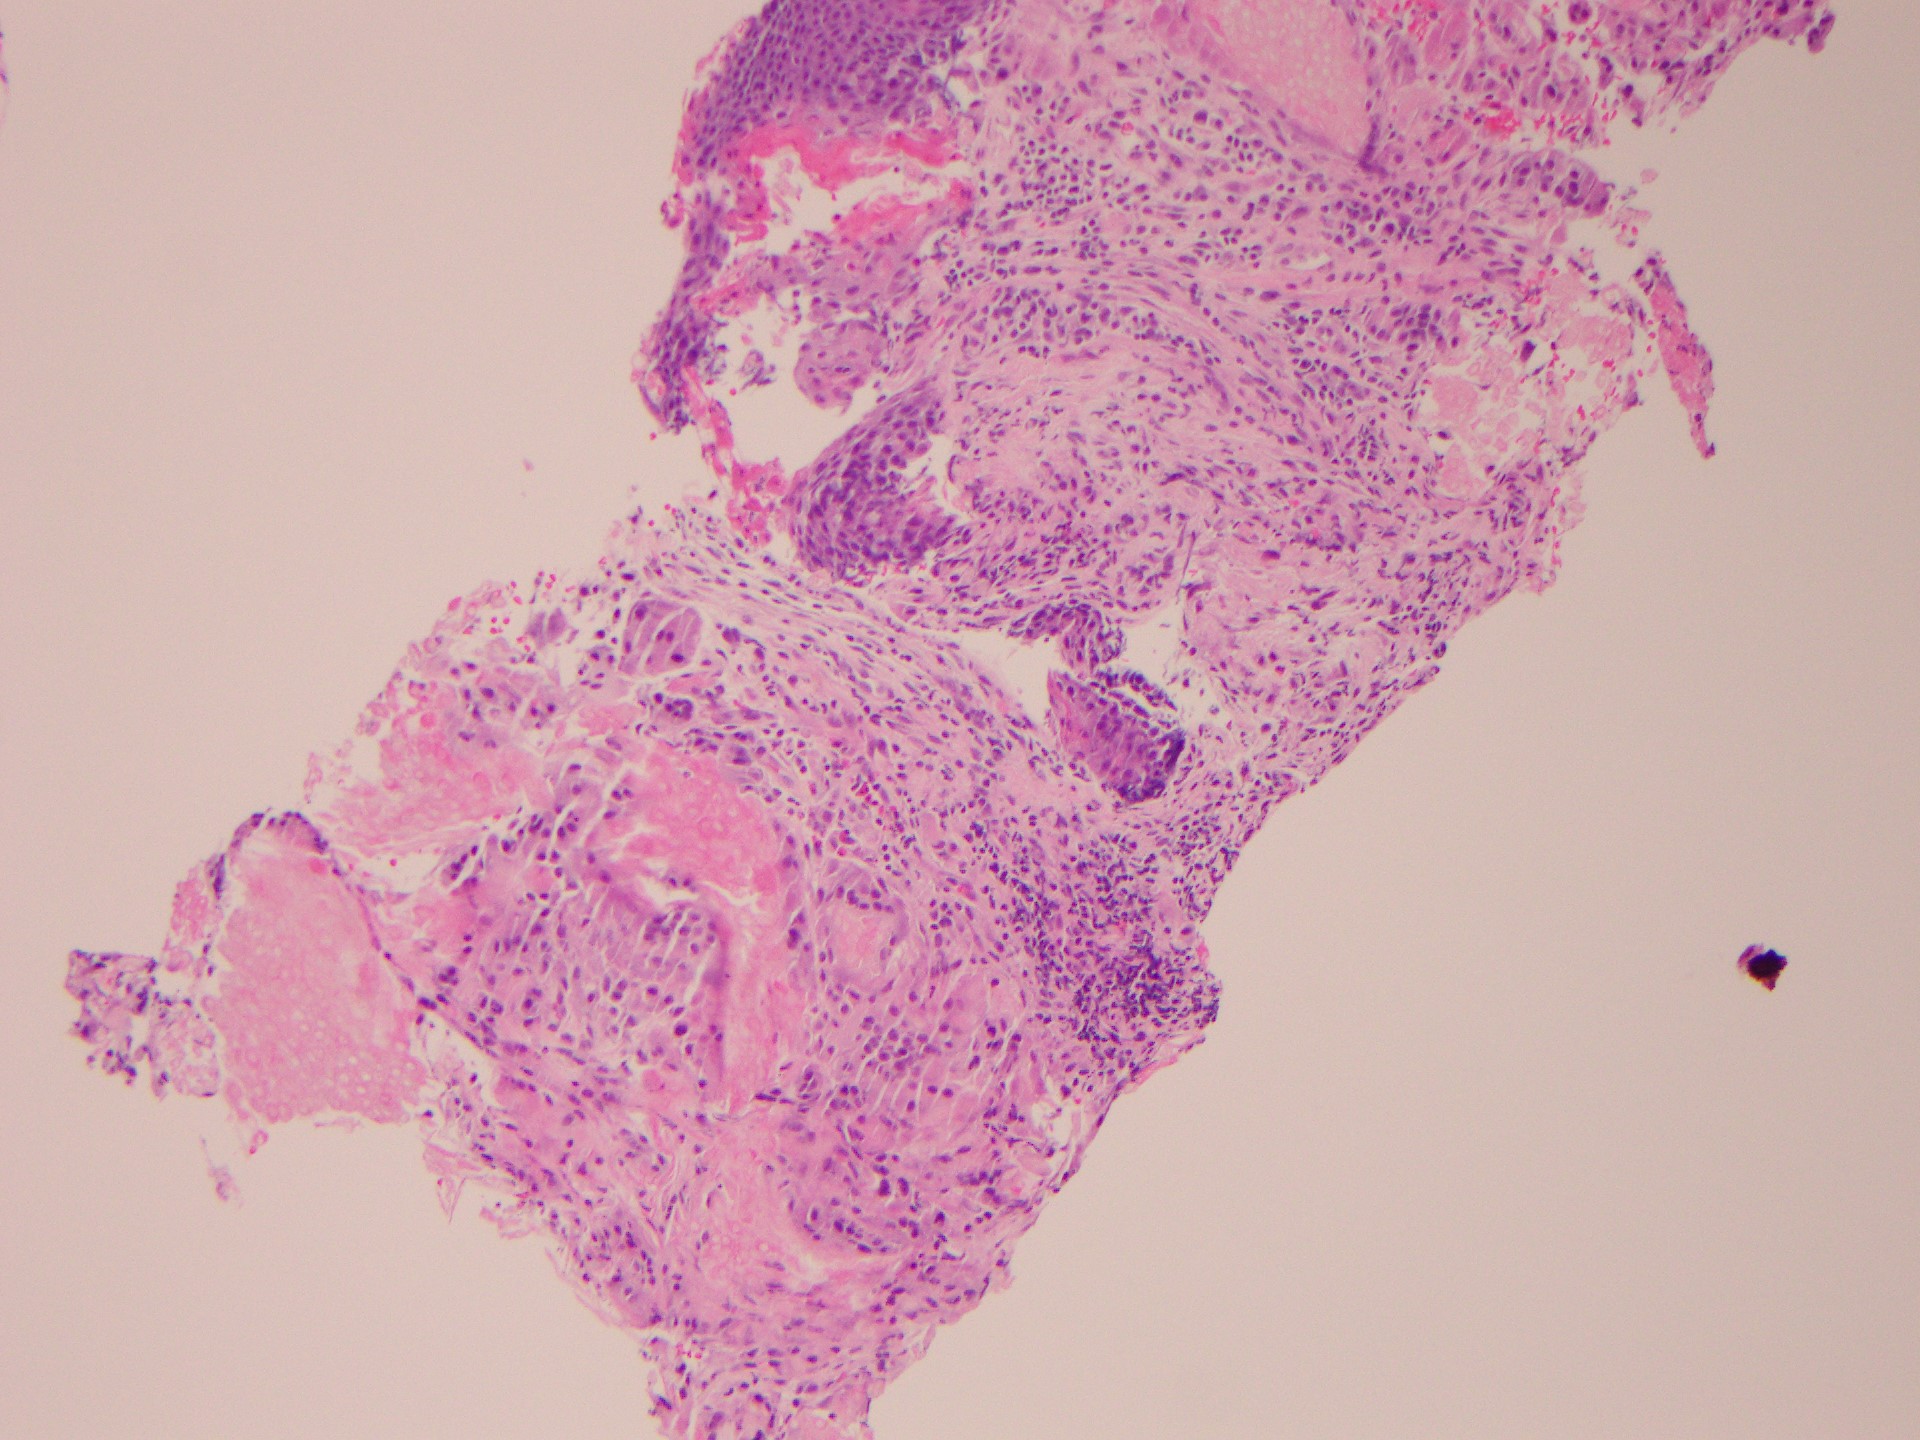

The ultrasound-guided biopsy was negative for malignancy, but the results revealed fragments of pilomatricoma (Figures 2 and 3).

Figures 2 and 3. Anucleated ghost (or shadow) cells with foreign-body reaction at the periphery (hematoxylin-eosin, original magnification ×40).